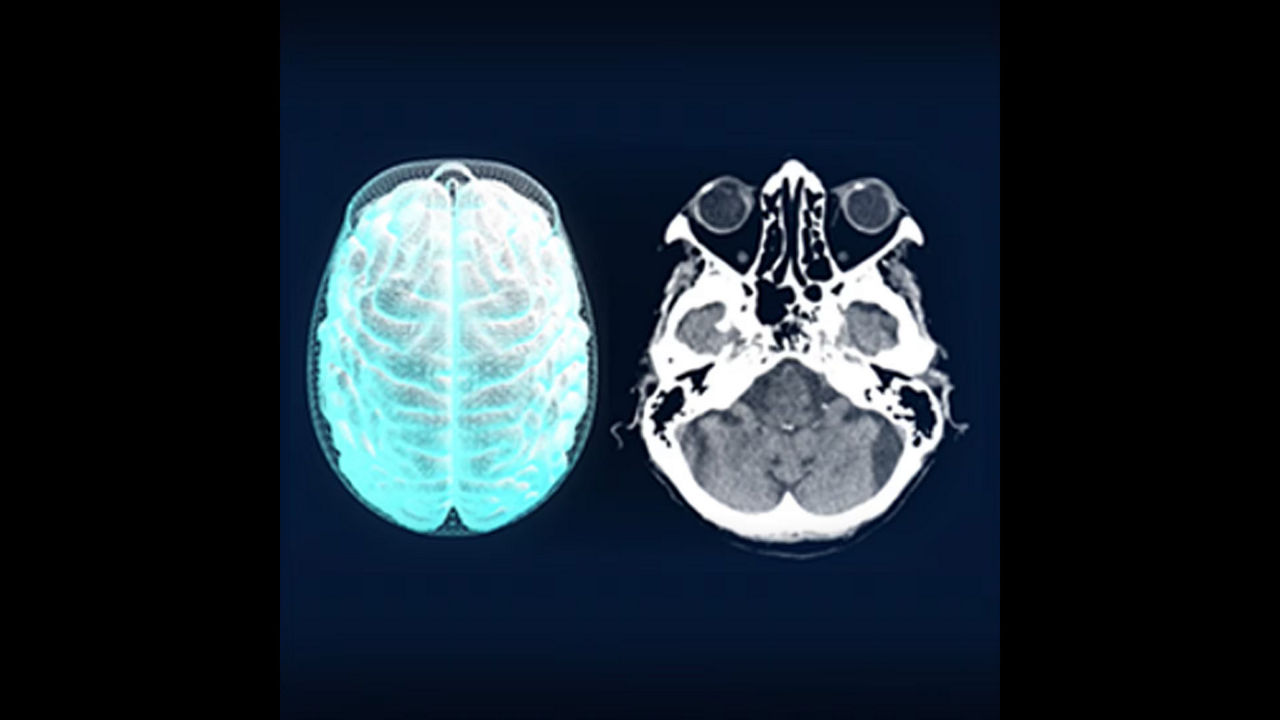

Simplify the Stroke CT workflow and the communication within the stroke team.

<p>FastStroke with StrokeSENS<sup>3</sup></p>

<p>CT Perfusion 4D Neuro</p>

<p>Dynamic Shuttle</p>